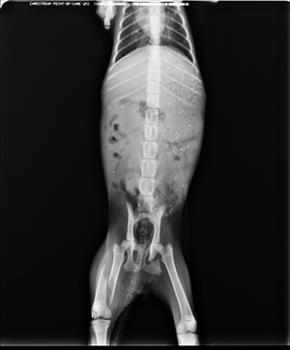

Wie man auf den Röntgenaufnahmen erkennen kann, hat er einen gebrochenen Oberschenkelknochen. Das Becken und die Hüfte werden heute noch mal von einem Spezialisten genauer untersucht. Am Kinn und im Mundbereich hat er außerdem eine Wunde und starken Schnupfen. Er bekommt nun Medikamente.